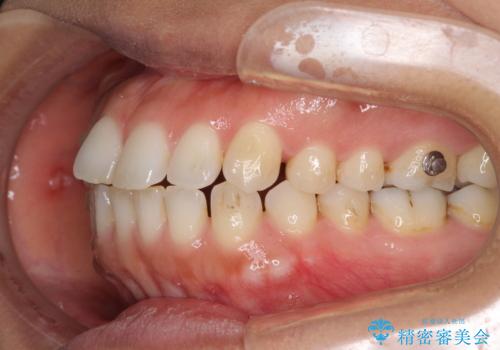

受け口傾向の前歯 すきっ歯の改善

- 前歯の隙間と口元の突出感を気にして来院された患者様です。

嚥下時に舌を突出させる癖があり、成長期に下顎が有意に成長し、歯と歯の間に隙間ができてしまいました。

舌の癖を改善し、インビザラインにて治療を行うこととしました。

舌癖を改善したことで、隙間や突出感を改善することができました。

隙間は後戻りしやすいため、舌側を細いワイヤーで固定することとしました。